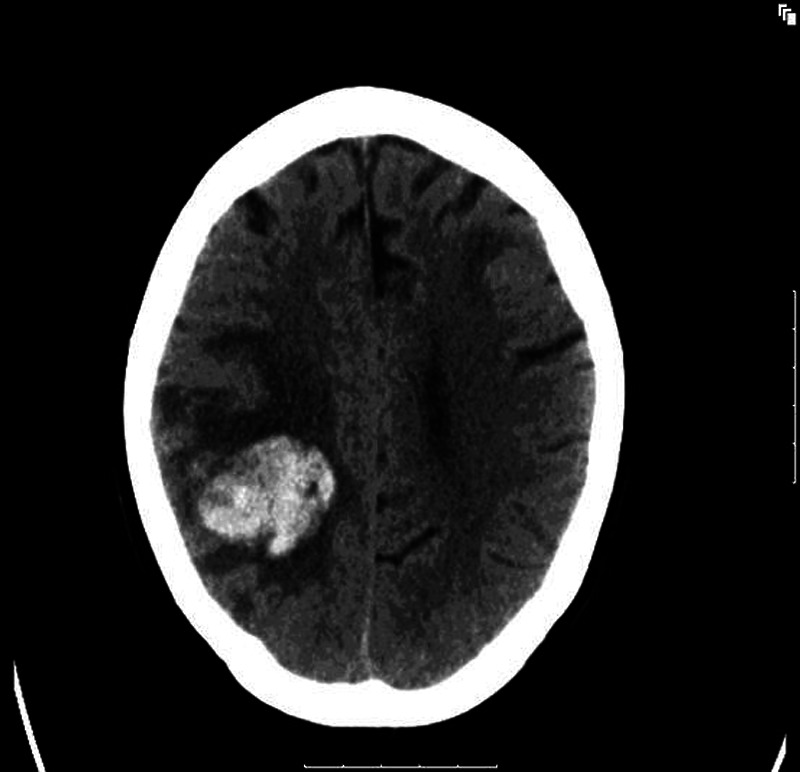

The patient stabilised on ECMO and an altered course of antibiotics. ECMO was decannulated 10 days later. Two days later she was slow to wean from sedation and a CT head was performed. Unfortunately this showed acute haemorrhage in the right parietal region with surrounding oedema and compression of the lateral ventricles. There were also similar smaller regions of acute haemorrhage in left and right temporal lobes (figures 1 and 2). She was repatriated to ICU at the referral hospital 14 days later.

Figure 1.

Initial CT head on intensive care unit showing acute haemorrhage in right parietal region.